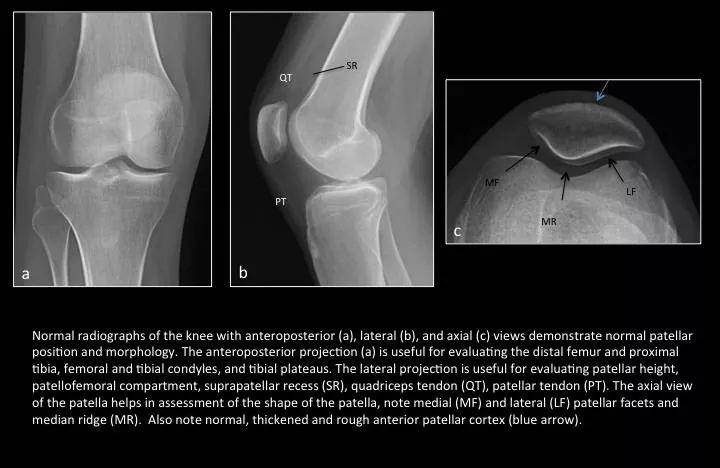

Fig. 1: Normal knee radiographs

图1:正常膝关节